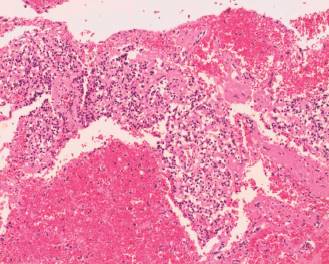

En el procedimiento quirúrgico se logró la resección completa de la tumoración y del polo inferior de bazo por presentar adherencias a cápsula esplénica. Procedimiento sin complicaciones. En el estudio macroscópico la pieza de resección pesó 330 g; al corte era quística con contenido friable, pardo-rojizo oscuro (Figura 2). Las secciones histológicas mostraron amplias áreas de necrosis y hemorragia entre las que se reconocía una proliferación celular atípica que se disponía en patrón pseudopapilar con células poco cohesivas, poligonales, de mediana talla; sus citoplasmas eran claros con ocasionales glóbulos hialinos (Figura 3). Se evidenciaron núcleos con hendiduras y cromatina en grumos, se observaron escasas mitosis típicas. El estroma presentaba áreas hialinizadas, acúmulos de macrófagos espumosos y escasas espículas de colesterol (Figura 4). Las técnicas de inmunohistoquímica mostraron positividad para enolasa, CD56, Fli-1, betacatenina (Figura 5) y vimentina, siendo negativo para sinaptofisina y cromogranina. Basados en estos hallazgos se realizó diagnóstico anatomopatológico de tumor sólido pseudopapilar de páncreas. Los bordes de resección y el parénquima esplénico se encontraban libres de lesión.

Figura 3: Proliferación con patrón seudopapilar, estroma focalmente hialinizado y amplias áreas de hemorragia (HE, 40 X).